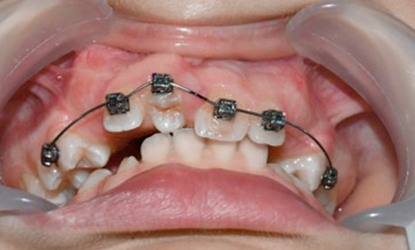

>   Autotransplantacja w miejsce 11 – przeniesienie własnego zęba pacjenta w celu uzupełnienia brakującego zęba w przednim odcinku szczęki.

Po stronie dawcy, czyli w miejscu usuniętego zęba przedtrzonowego, założono specjalny aparat ortodontyczny, który stabilizował przestrzeń i zapobiegał przesunięciom sąsiednich zębów.

>   Zdjęcia pokazują pacjentkę przed i po zabiegu autotransplantacji, a także zmiany w położeniu tkanek miękkich. Po przeprowadzeniu zabiegu, który miał na celu uzupełnienie brakującego zęba siecznego lewego. Osiągnięte zostało poszerzenie i uwypuklenie się okolicy podnosowej.